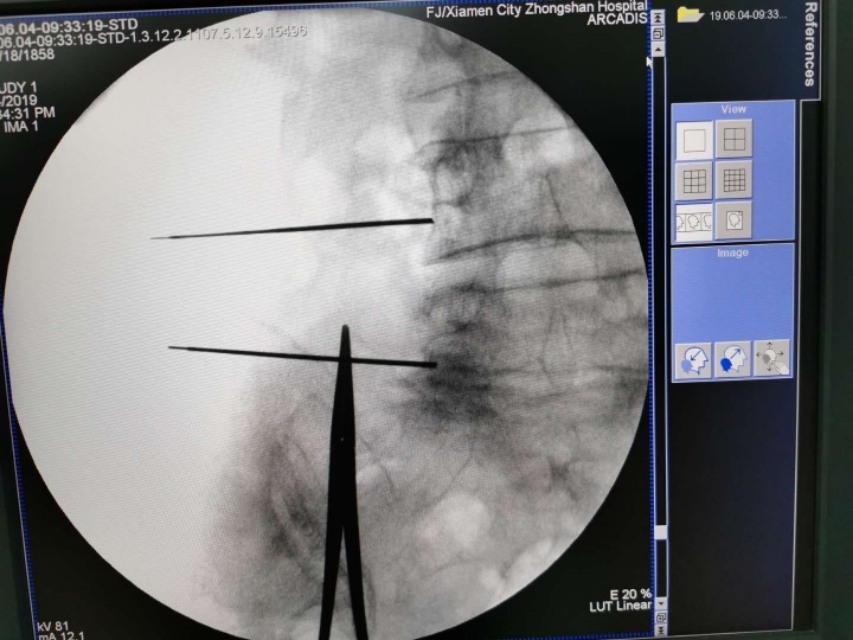

C臂透视左侧斜位片。腰4、腰5骶1左侧附件成苏格兰犬状。确定进针点。

在C臂辅助下穿刺针顺利到达目标靶点safety triangle